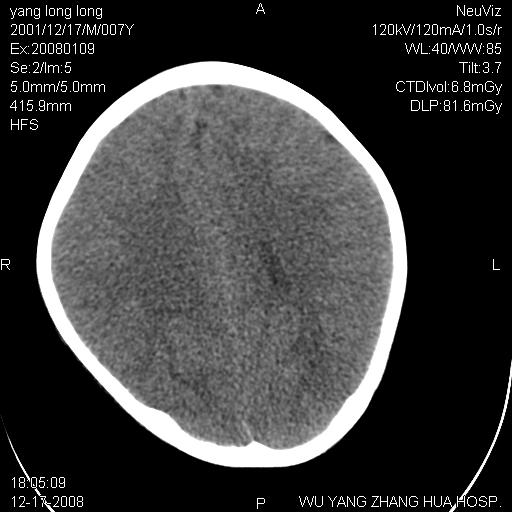

标题: PED1686:M7Y,头外伤,家人及自诉平时无任何不适。 [打印本页]

标题: PED1686:M7Y,头外伤,家人及自诉平时无任何不适。

考虑蛛网膜囊肿,请老师们看看多指导指导。

多考虑大枕大池。本例颅骨歪歪的,灶后枕骨似有膨胀征像(为蛛网膜囊肿征像),但整个左侧枕叶后方枕骨均有向后膨隆,所以暂不考虑蛛网膜囊肿。必要时随访

鉴别巨大枕大池与蛛网膜囊肿之间,倾向前者。